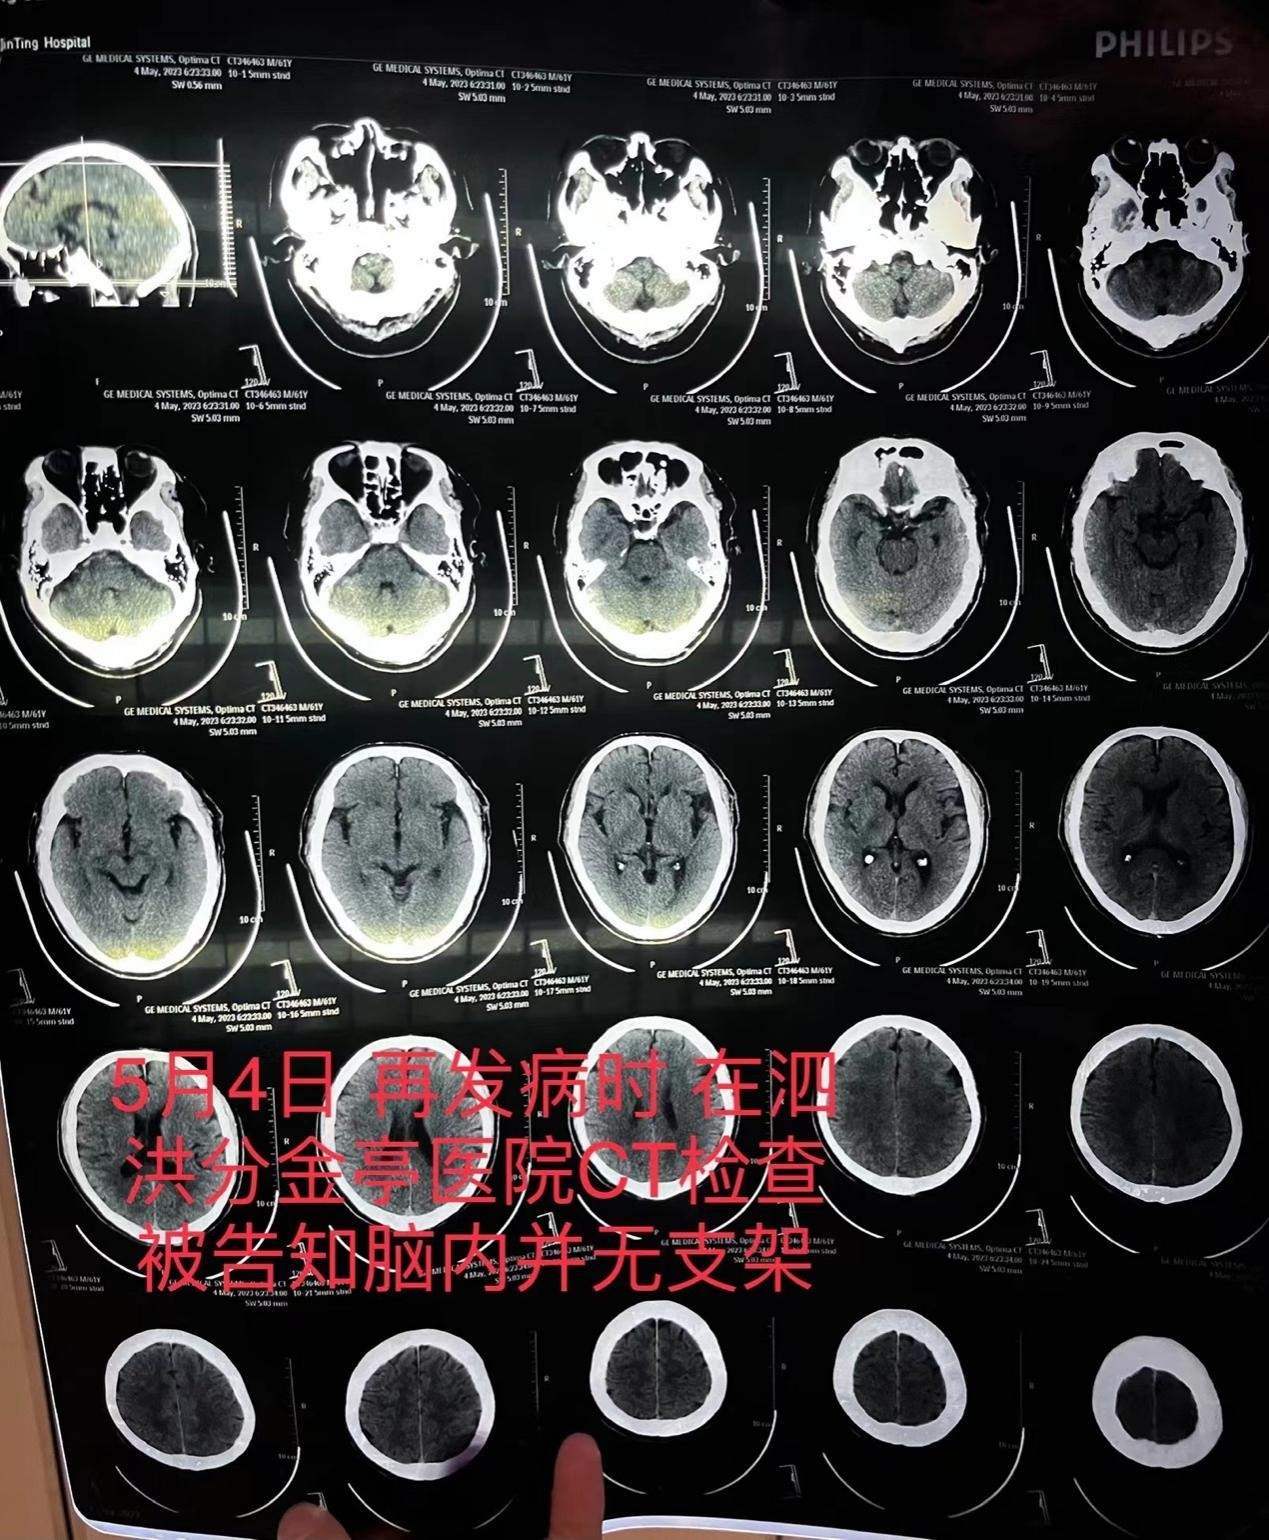

5月4日,朱老漢突發嚴重腦梗。他先被救護車送至江蘇省宿遷市泗洪縣分金亭醫院搶救。令家屬沒想到的是,當時的CT檢查發現,其顱內段部分動脈已嚴重堵閉,同時未發現此前植有支架。“我們當時不相信這個檢查結果,認為這是小醫院,可能檢查不出來,所以我們決定轉送到之前的醫院。”朱先生説,朱老漢又被轉入宿遷第一人民醫院,曾作為主刀醫生的齊某此時才承認,之前未能在患者顱內血管成功植入支架。

朱老漢在泗洪縣分金亭醫院的CT檢查報告,顯示顱內並無支架。朱先生供圖